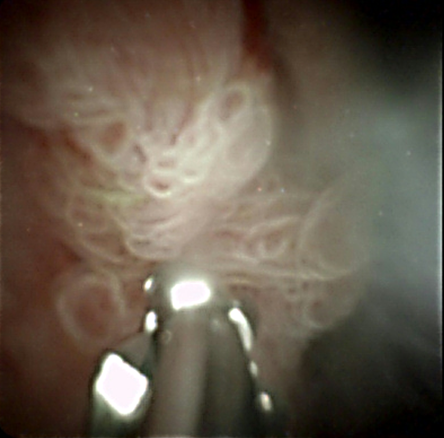

膵管内乳頭粘液性癌(IPMC)が疑われた症例です。

主膵管内の病変を詳しく評価し、腫瘍が膵管内のどこまで広がっているかを直視下でより正確に判断することが重要と考えられました。そこで、膵管鏡を用いて膵管内を直接観察しました。

経口膵管鏡で観察すると、膵頭部の主病変から尾側方向へ乳頭状病変の進展所見を認めました。膵体部および膵尾部の主膵管への病変の進展は認めませんでした。

このように、膵管鏡を使用することで腫瘍の進展範囲をより正確に評価することができました。

これらの内視鏡検査の結果をもとに手術の切除範囲を慎重に検討し、膵頭十二指腸切除術を行いました。術後の病理検査でも病変は完全に切除されており、根治切除を行うことができました。